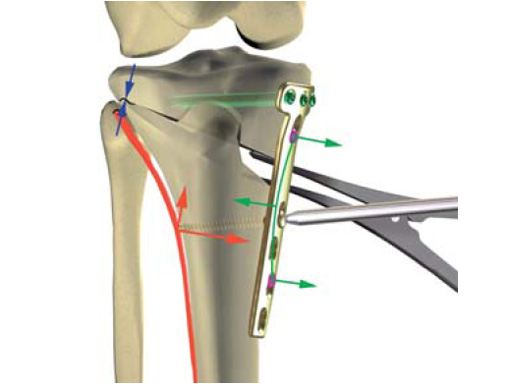

The precontoured plate now has a chamfer at the proximal part and rounded edges at the lateral rims of the plate. A MIPO tapered end at the distal end was added to have a smoother pass to the bone. The two upper LCP holes in the distal part were slightly repositioned in line with the axis of the plate to eliminate the rotation of the plate during compression with cortex screws because of the former asymmetrical alignment of the holes. The two most distal LCP holes were changed to isolated LCP holes to hinder the use of cortex screws.

The correction is planned on a long-leg standing x-ray. After surgery, the mechanical axis should pass through a point 63% on the lateral side of the total width of the tibial plateau in the frontal plane. A transverse or slightly oblique incision is used to avoid damage to the saphenous nerve. The distal fibers of the medial collateral ligament are detached from the tibia. Under fluoroscopic control, two wires are placed in the proximal tibia marking the transverse osteotomy plane. The cut usually starts at the upper margin of the pes anserinus and ends at the tip of the fibula on the lateral side. The wires are placed exactly parallel to the tibial plateau thus taking into consideration the individual tibial slope of the patient. An incomplete cut of the posterior two-thirds of the proximal tibia is performed with an oscillating saw guided by the wires. Continuous irrigation avoids burn injury to the bone. A second osteotomy is now performed in the anterior third of the tibia in an angle of 100 ending above the patellar tendon insertion. A smaller saw blade is used and the complete anterior cortex is cut exactly in the frontal plane. The osteotomy is now gradually opened by inserting flat chisels or a spreader-chisel into the posterior osteotomy cleft. This process may take some minutes and can usually be completed without fracture of the lateral cortex. A bone spreader is now placed in the posteromedial edge of the tibia and the chisels are removed. The leg is extended and the correction is checked with the fluoroscope. A long metal rod is placed between center of the hip joint and center of the ankle joint. The projection of this rod should be at the planned point of correction on the tibial plateau lateral of the midline. Eccentric collapse of the medial joint space may cause accidental overcorrection. In this case pressure on the foot may simulate loading and body weight. The correction can be fine-tuned by opening or closing the spreader. The TomoFix Medial Tibia Plate is now placed in a subcutaneous pocket. The implant is precontoured and usually fits well to the bone surface. The distance holders avoid compression of the medial collateral ligament and the pes anserinus. Three proximal bolts are placed near the subchondral sclerosis zone. The position of the bolts is adapted to the anatomy of the proximal tibia giving optimum purchase for the bolts. An oblique lag screw is inserted distal to the osteotomy. This screw in the first combination hole allows careful compression of the lateral osteotomy hinge and pretensioning of the implant. A stab incision is created on the shaft and the implant is fixed monocortically with bolts. The lag screw and the distance holders are replaced by bolts. The medial collateral ligament is released longitudinally to reduce medial compartment pressure and the wound is closed in layers. An overflow drain may be used. Clinical and experimental work has proven that when this technique is closely followed, corrections up to and over 15 mm can be performed without bone grafting or use of bone substitutes.

The KNEG is working on further improvements to the implants. The TomoFix Medial Tibia Shaft will get slimmer, as the combination holes on the shaft will be exchanged against simple locking holes. The edges will be rounded to help avoid morbidity from the implant. These design modifications have been tested biomechanically and no disadvantages have been recognized against the present plate design. In addition, a smaller version of the plate is presently in preparation, mainly adapted to the specific anatomy of the Asian proximal tibia. Development of this plate is strongly supported by the input of our Japanese friends R Takeuchi and T Sawaguchi. First prototypes will undergo biomechanical testing in the near future.